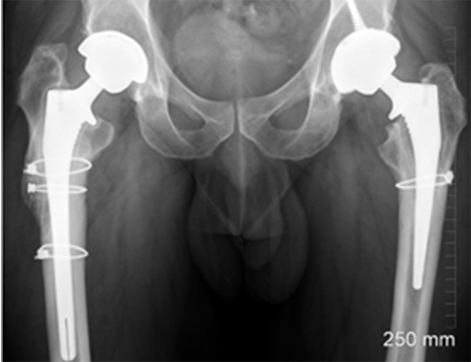

This case involves a 67-year-old gentleman who faced a series of complications due to hip trauma he had experienced over 50 years ago. After his primary and revision surgeries, and subsequent three hip replacements, he was left with a failing hip implant. His most recent hip replacement lasted 13 years before massive circumferential acetabular osteolysis caused the cup to loosen. Imaging revealed anterior and medial wall deficiencies, while the posterior column remained intact. The patient had a metal-on-polyethylene (MoP) bearing, which over time led to the wear of the polyethylene liner, triggering an inflammatory reaction and bone loss due to polyethylene debris.

The surgical plan required a custom 3D-printed acetabular cup, designed specifically for the patient's anatomy. The implant was designed with three flanges for optimal fixation. The surgery involved a posterior approach, with meticulous bone preparation to minimize further bone loss and ensure the custom implant fit securely.

This case represents ALTR with MoP. ALTR was characterized by massive osteolysis of the pelvic bone, which was most likely caused by polyethylene wear debris. This case underscores the complexity of revision hip surgeries and highlights the value of custom 3D-printed implants for achieving secure fixation and improving patient outcomes despite significant bone loss. Update at 7 years post operative is that the patient has excellent hip function and more can be seen in this paper: